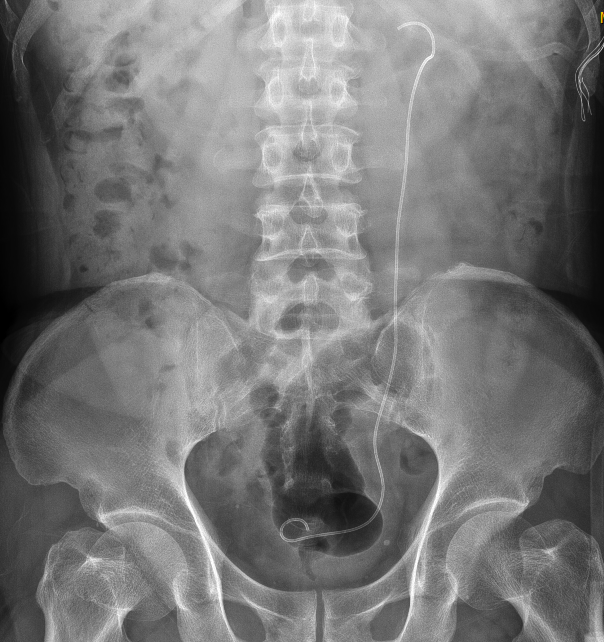

张先生术后复查X片,结石已完全清除干净

很幸运的是,许清泉教授十分擅长复杂泌尿系统结石的诊断与治疗,尤其在复杂泌尿系结石的腔内碎石手术方面经验丰富,这让张先生和家人十分放心。他为张先生定制了“左侧经皮肾镜取石”方案。手术中,他精准定位,运用“双镜联合”技术,一口气把结石清得干干净净!

术后,张先生恢复很快,3天后康复出院。